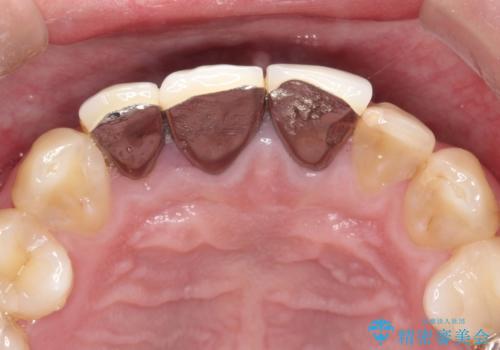

保険適用のかぶせ物が装着されており、適合も悪く、変色している状態でした。

土台からの、再治療を行い、オールセラミッククラウンの装着を行う計画としました。